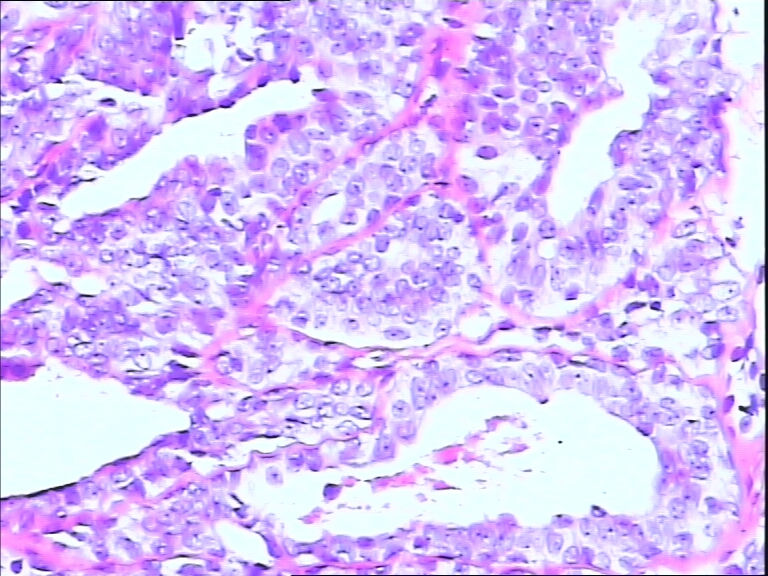

42y

左乳头有3mm结节

灰白不整形组织一块:0.7*0.5*0.4

导管内乳头状肿瘤